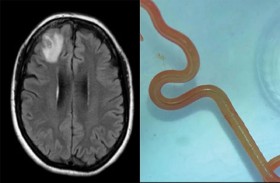

دودة حية في دماغ امرأة

تم اكتشاف أول حالة إصابة في العالم بعدوى طفيلية جديدة في إنسان، بعد العثور على دودة مستديرة حية يبلغ طولها 8 سنتيمترات في دماغ امرأة أسترالية. وتم سحب الدودة المستديرة “أوفيداسكاريس روبرتسي” ... إقرأ المزيد